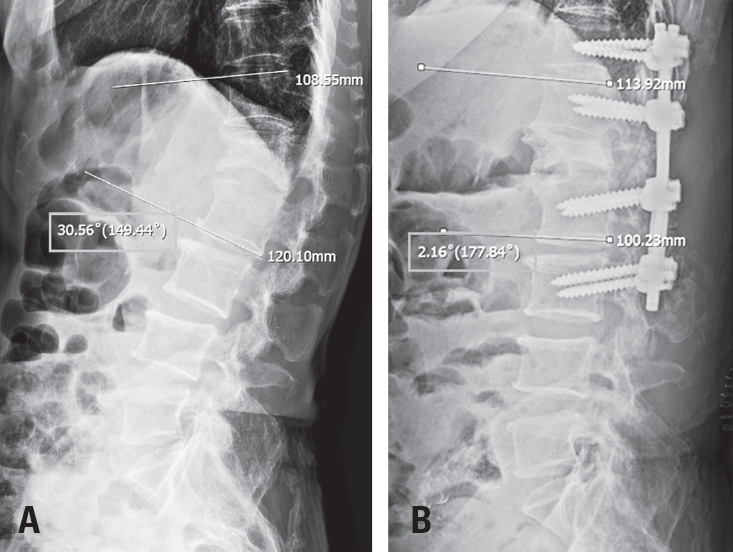

Tethered cord syndrome (TCS) is a condition in which the spinal cord becomes pathologically stretched due to various congenital or acquired etiologies, leading to progressive neurological symptoms. While surgical detethering is the gold standard for pediatric patients, adult-onset recurrent TCS presents a significant surgical challenge. Reoperation carries substantial risks—including spinal cord injury, cerebrospinal fluid leakage, and a high rate of retethering—often resulting in suboptimal long-term outcomes. Recently, spine-shortening osteotomy (SSO) has emerged as an alternative technique to reduce spinal cord tension without direct manipulation of the neural elements. Here, we report a case of recurrent adult TCS associated with a lipomyelomeningocele, which was exacerbated by post-traumatic kyphosis from an L1 compression fracture. The patient was successfully treated with SSO at the L1 level. This case highlights the utility of SSO as a safe and effective alternative to conventional revision detethering, particularly in complex cases involving spinal deformity.

Spine-Shortening Osteotomy for Recurrent Adult Tethered Cord Syndrome Exacerbated by Traumatic Kyphosis: A Case Report

Seohong Min, Jae Min Kim, Dongkyu Kim, Bongju Moon, Jeong-Yoon Park, Kyung Hyun Kim, Sung-Uk Kuh, Dong-Kyu Chin, Keun-Su Kim, Hyun-Jun Jang

J Adv Spine Surg 2025;15(2):119-124.   Published online December 31, 2025

DOI: https://doi.org/10.63858/jass.15.2.119